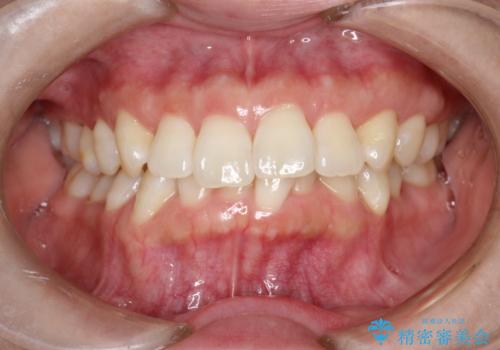

インビザライン ライトパッケージによる部分矯正治療 下の前歯のみの歯並び改善

- インビザライン ライトパッケージパーシャル(下顎のみ)

- 下の前歯の歯並びのみの改善をご希望されました。

インビザライン ライトパッケージ下顎のみ(1枚~14枚まで)での治療を行なっていきました。

マウスピース枚数 初回14枚 + 追加13枚

概ね7ヶ月で治療完了しました。

インビザラインのライトパッケージでは14枚までという枚数制限がありますが、限られた枚数の中で当院独自の工夫を随所に盛り込み、狙い通りの治療結果が得られました。